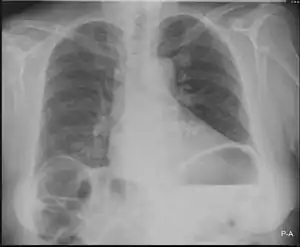

![]() | |

| Chest X-ray showing obvious Chilaiditi's sign, or presence of gas in the right colic angle between the liver and right hemidiaphragm. | |